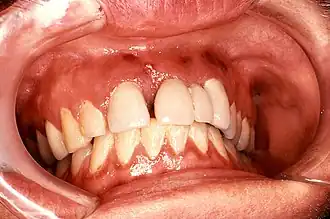

Das Kaposi-Sarkom kann sich in die regionalen Lymphknoten ausbreiten, was manchmal zu ausgeprägten Lymphödem der abhängigen (distalen) Extremitätenabschnitte führen kann. Bei einer disseminierten Ausbreitung im ganzen Körper kann es auch zu Beteiligung von Mund, Magendarmtrakt, Urogenital-Trakt und inneren Organen mit der Gefahr gastrointestinaler Blutungen und Bluterbrechen (Hämatemesis) kommen. Bei Beteiligung der Lungen kann es zum Bluthusten (Hämoptyse) kommen. Im Mund finden sich oftmals recht kleine und unauffällige lividen Flecken vor allem am harten und weichen Gaumen, am Zahnfleisch und an der Backenschleimhaut.[3]